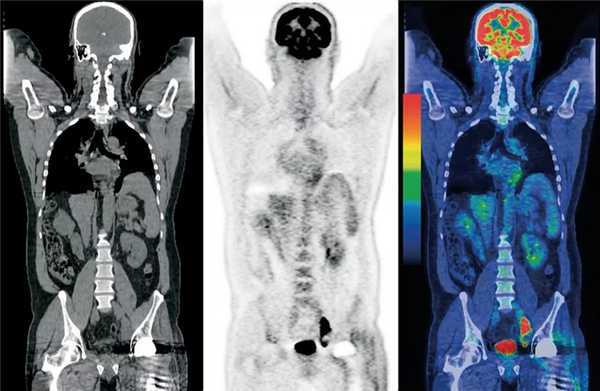

Оценка отдаленных метастазов

Рак молочной железы часто дает отдаленные метастазы в легкие, печень и кости. Преимуществом ПЭТ всего тела перед традиционными методами диагностики, такими как рентгенография органов грудной клетки, сцинтиграфия скелета и УЗИ органов брюшной полости, является возможность обнаружения отдаленных метастазов в различных областях тела и органах во время одного исследования. Было обнаружено (Moon et al.), что ПЭТ всего тела обладает высокой диагностической точностью в отношении пациенток, у которых имеется подозрение на рецидив рака или на метастатическое поражение. На основании количества обнаруженных очагов чувствительность метода в обнаружении отдаленных метастазов составила 85%, а специфичность 79%.

Множественные отдаленные метастазы у 44-летней пациентки, страдающей раком обеих желез. А: на ПЭТ определяются множественные зоны гиперметаболизма ФДГ в грудной клетке и брюшной полости. B, C: на ПЭТ обнаружены также зоны гиперметаболизма ФДГ в обеих молочных железах (отмечены белыми стрелками на томограмме B), в лимфоузлах средостения (отмечены черными стрелками на томограмме B), и во внутренних органах (отмечены стрелками на томограмме C).

Изображения иллюстрируют контроль химиотерапии у 35-летней пациентки, страдающей раком молочной железы с метастазами в кости. A-C: на ПЭТ, выполненной изначально (A, B) и ПЭТ-КТ (C) определяется в значительной степени выраженный гиперметаболизм ФДГ в обоих молочных железах и во многих позвонках. D-F: на контрольной ПЭТ (D, E) и ПЭТ-КТ (F), выполненных спустя три курса химиотерапии, определяется существенное снижение гиперметаболизма ФДГ в обоих молочных железах и позвонках.